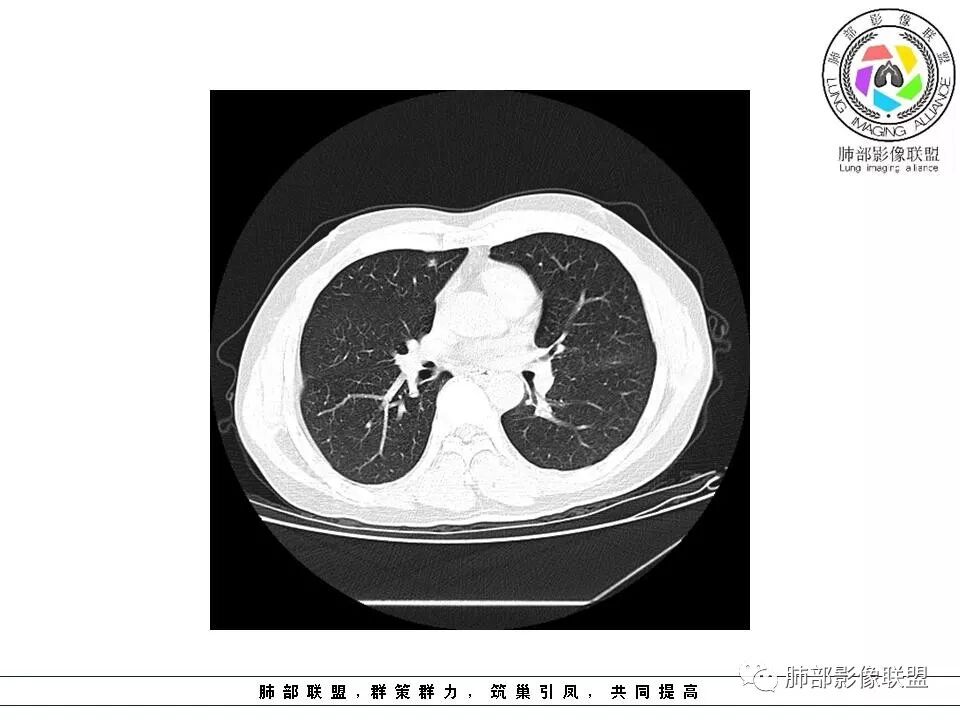

南边:51岁男性,体检发现右肺结节这个年龄段的男性,啥都可以发生,也属于肺癌的高危人群南边:首先是实性还是GGO?好像实性吧

如果实性病变,边缘收缩,可以考虑炎性, 但是边缘有边界清楚GGO,一定要警惕恶性,还有粗短毛刺更要小心撇开其它,看到这个图,除非你怀疑假象,不然就是要考虑腺癌的可能

边界清楚GGO,短毛刺,这要小心瘢痕癌可以多为腺癌复查没变化,与血供有关,属于休眠期张国祯教授的理论:腺瘤样增生、原位癌都属于偏良性,就是没有侵袭性;以后发展——侵袭可以,不变可以,部分可能还会凋亡(比较少)

原位腺癌

这个病例,它是边缘有一些恶性的特点出来了,但是可能重点关注的部位不同。专注于那些实性成分去了,没看到边缘征像。他确实有一些良性的征像在那里,恶性迹象不明显,或者某些层面出现恶性征像。